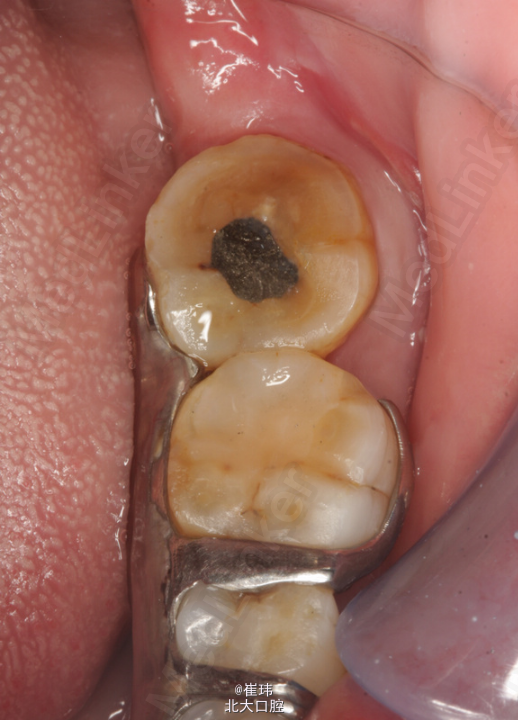

患者女,48岁 左下后牙反复疼痛4个月,自发痛伴夜间加重2天。 “一疼起来攒得半边脸都疼”。 左下后牙4年前曾于外院充填治疗

37O :银汞充填体,边缘良好,叩(±),不松,龈未见明显异常。冷测无反应。 36DO : 牙色充填体,边缘良好,叩(-),不松,龈未见明显异常。 X片示37: 充填体达根管口,未见根充影像根尖周未见明显异常 左上后牙固定修复体 27O 探及一深龋洞,色黑,质软,叩痛(+),不松,龈未见明显异常,冷测激发痛。修复科拆除26,27牙冠,拆除牙冠后见近中舌及远中颊合面深大龋洞,探敏感,质软

诊断:慢性牙髓炎急性发作